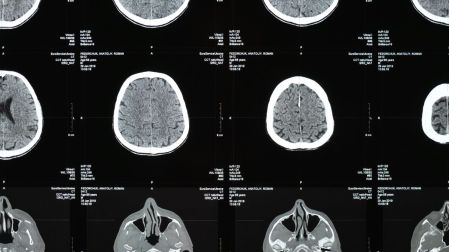

El proceso comenzó con imágenes de resonancia magnética funcional (fMRI) tomadas antes de la amputación, mientras los participantes realizaban movimientos con la mano que sería amputada y con los labios (una región cercana en el mapa cerebral).

Sorprendentemente, las áreas del cerebro previamente asociadas con el movimiento de esa mano continuaban activándose casi de la misma manera que antes de la amputación.

Los investigadores encontraron que no hubo tal expansión, lo que refuerza la idea de que el cerebro mantiene una representación estable del cuerpo, incluso de partes que ya no existen físicamente.